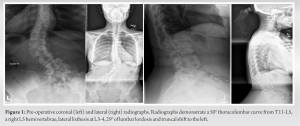

Pre-operative extension radiographs of the lumbar spine (Fig. 1) and computed tomography (CT) imaging (Fig. 2) demonstrated thoracolumbar curve measuring approximately 50° from T11-L5, a right hemivertebrae at L5, a 9 mm of lateral listhesis at L3-4, 15° of lumbar lordosis, and asymmetric disc height loss from L1-S1.

Pre-operative planning was performed through the Aprevo software (Carlsmed, Carlsbad, CA) and a 3D reconstruction was performed. Customized 3D printed titanium implants were computationally constructed using pre-operative CT images (Fig. 3 and 4).

The objectives of this study were to (1) illustrate an example of successful surgical treatment of a patient with hemivertebrae using custom patient-specific implants at multiple spinal levels and (2) compare this case a to a similar case that utilized standard implants. The patient in Case 1 suffered from chronic low back pain due to CS and a right wedge vertebra. Following lumbar decompression and fusion using customized 3D-printed implants, the patient reported significant improvement in her pain and posture (Fig. 6). Given the anatomic complexity of these patients, the development and utilization of customized implants allowed for an excellent endplate apposition without the need for extensive bony resection, which would not be possible with standard interbodies. To our knowledge, this is the first reported case demonstrating the treatment of CS using 3D-printed personalized spinal implants for multiple spinal levels. Studies evaluating the efficacy of personalized spinal implants are largely limited to case studies. Two of these studies reported the use of these implants in the treatment of congenital spinal disorders. Mobbs et al. [14] presented a 52-year-old woman with an 18-month history of back pain. Similar to our patient, their patient was found to have a congenital hemivertebra at L5 (Fig. 1 and 2) with degenerative changes that was treated with lumbar decompression and fusion with a personalized spinal implant. However, while only the L4/L5 segment was fused in Mobbs et al. case, the patient in our case underwent L3-S1 ALIF and posterior instrumentation T10-Pelvis (Fig. 4 and 5), demonstrating increased severity and unique complexity in our case. In another study [15], a 34-year-old man presented with a 3-year history of bilateral L5 radiculopathy caused by bilateral L5 pars defect, L5/S1 degenerative disc disease, and severe foraminal stenosis. Anterior lumbar interbody fusion surgery was performed with custom 3D interbodies. Again, our case differed from this case in complexity of procedure and medical history as we performed a multilevel deformity surgery using multilevel customized implants. To address our second objective, we compared Case 1 to Case 2, where the patient underwent an index lumbar decompression and fusion for CS (Fig. 7 and 8) using standard titanium implants. At 2-year post-operative, the patient in Case 2 presented with worsening sacroiliac pain with the evidence of rod fracture and pseudoarthrosis at L4-L5 (Fig. 9). Revision surgery resulted in improved pain and mobility (Fig. 10). Development of pseudoarthrosis and the need for revision surgery in Case 2 may be explained by the decreased surface area available for fusion, decreased contact of the implant with the bone, thus decreased on-growth and through-growth resulting in decreased osteointegration, and stability as compared to Case 1, which utilized custom implants. While larger, randomized, controlled studies are still needed to gain knowledge pertaining to long-term outcomes in comparison to traditional, non-customized implants, existing biomechanical and animal investigations of customized implants suggest they will provide improved outcomes and increased surgical safety and efficiency. In a study evaluating the biomechanical properties of titanium cages in cervical spine surgery, Fengbin et al. found that implants with increased end plate contact surface area resulted in decreased loss of height of fused segments, lower rate of subsidence, and lower scores of neck pain [16]. During an en bloc resection of L5 vertebral body with single lesion, Mobbs et al. compared reconstruction using a 3D patient-specific implant and an off-the-shelf implant at the same spinal level intraoperatively. The 3D patient-specific implant resulted in decreased time to implant, reduced radiographs required to determine the position of implant, improved end plate fit, and more uniform loading compared to the off-the-shelf implant [5]. From a safety perspective, 3D-implants seem to provide benefit over off-the-shelf implants as they avoid osteotomies required with off-the-shelf implants, thus decreasing operative time and blood loss, as well as allow for pre-planned screw trajectories which decrease the chance of damage to blood vessels, nerves, and the spinal cord [17]. The utility of 3D customized implants in allowing surgeons to operate on native anatomy will be safer, quicker, and result in increased osteointegration and bone/implant interface.